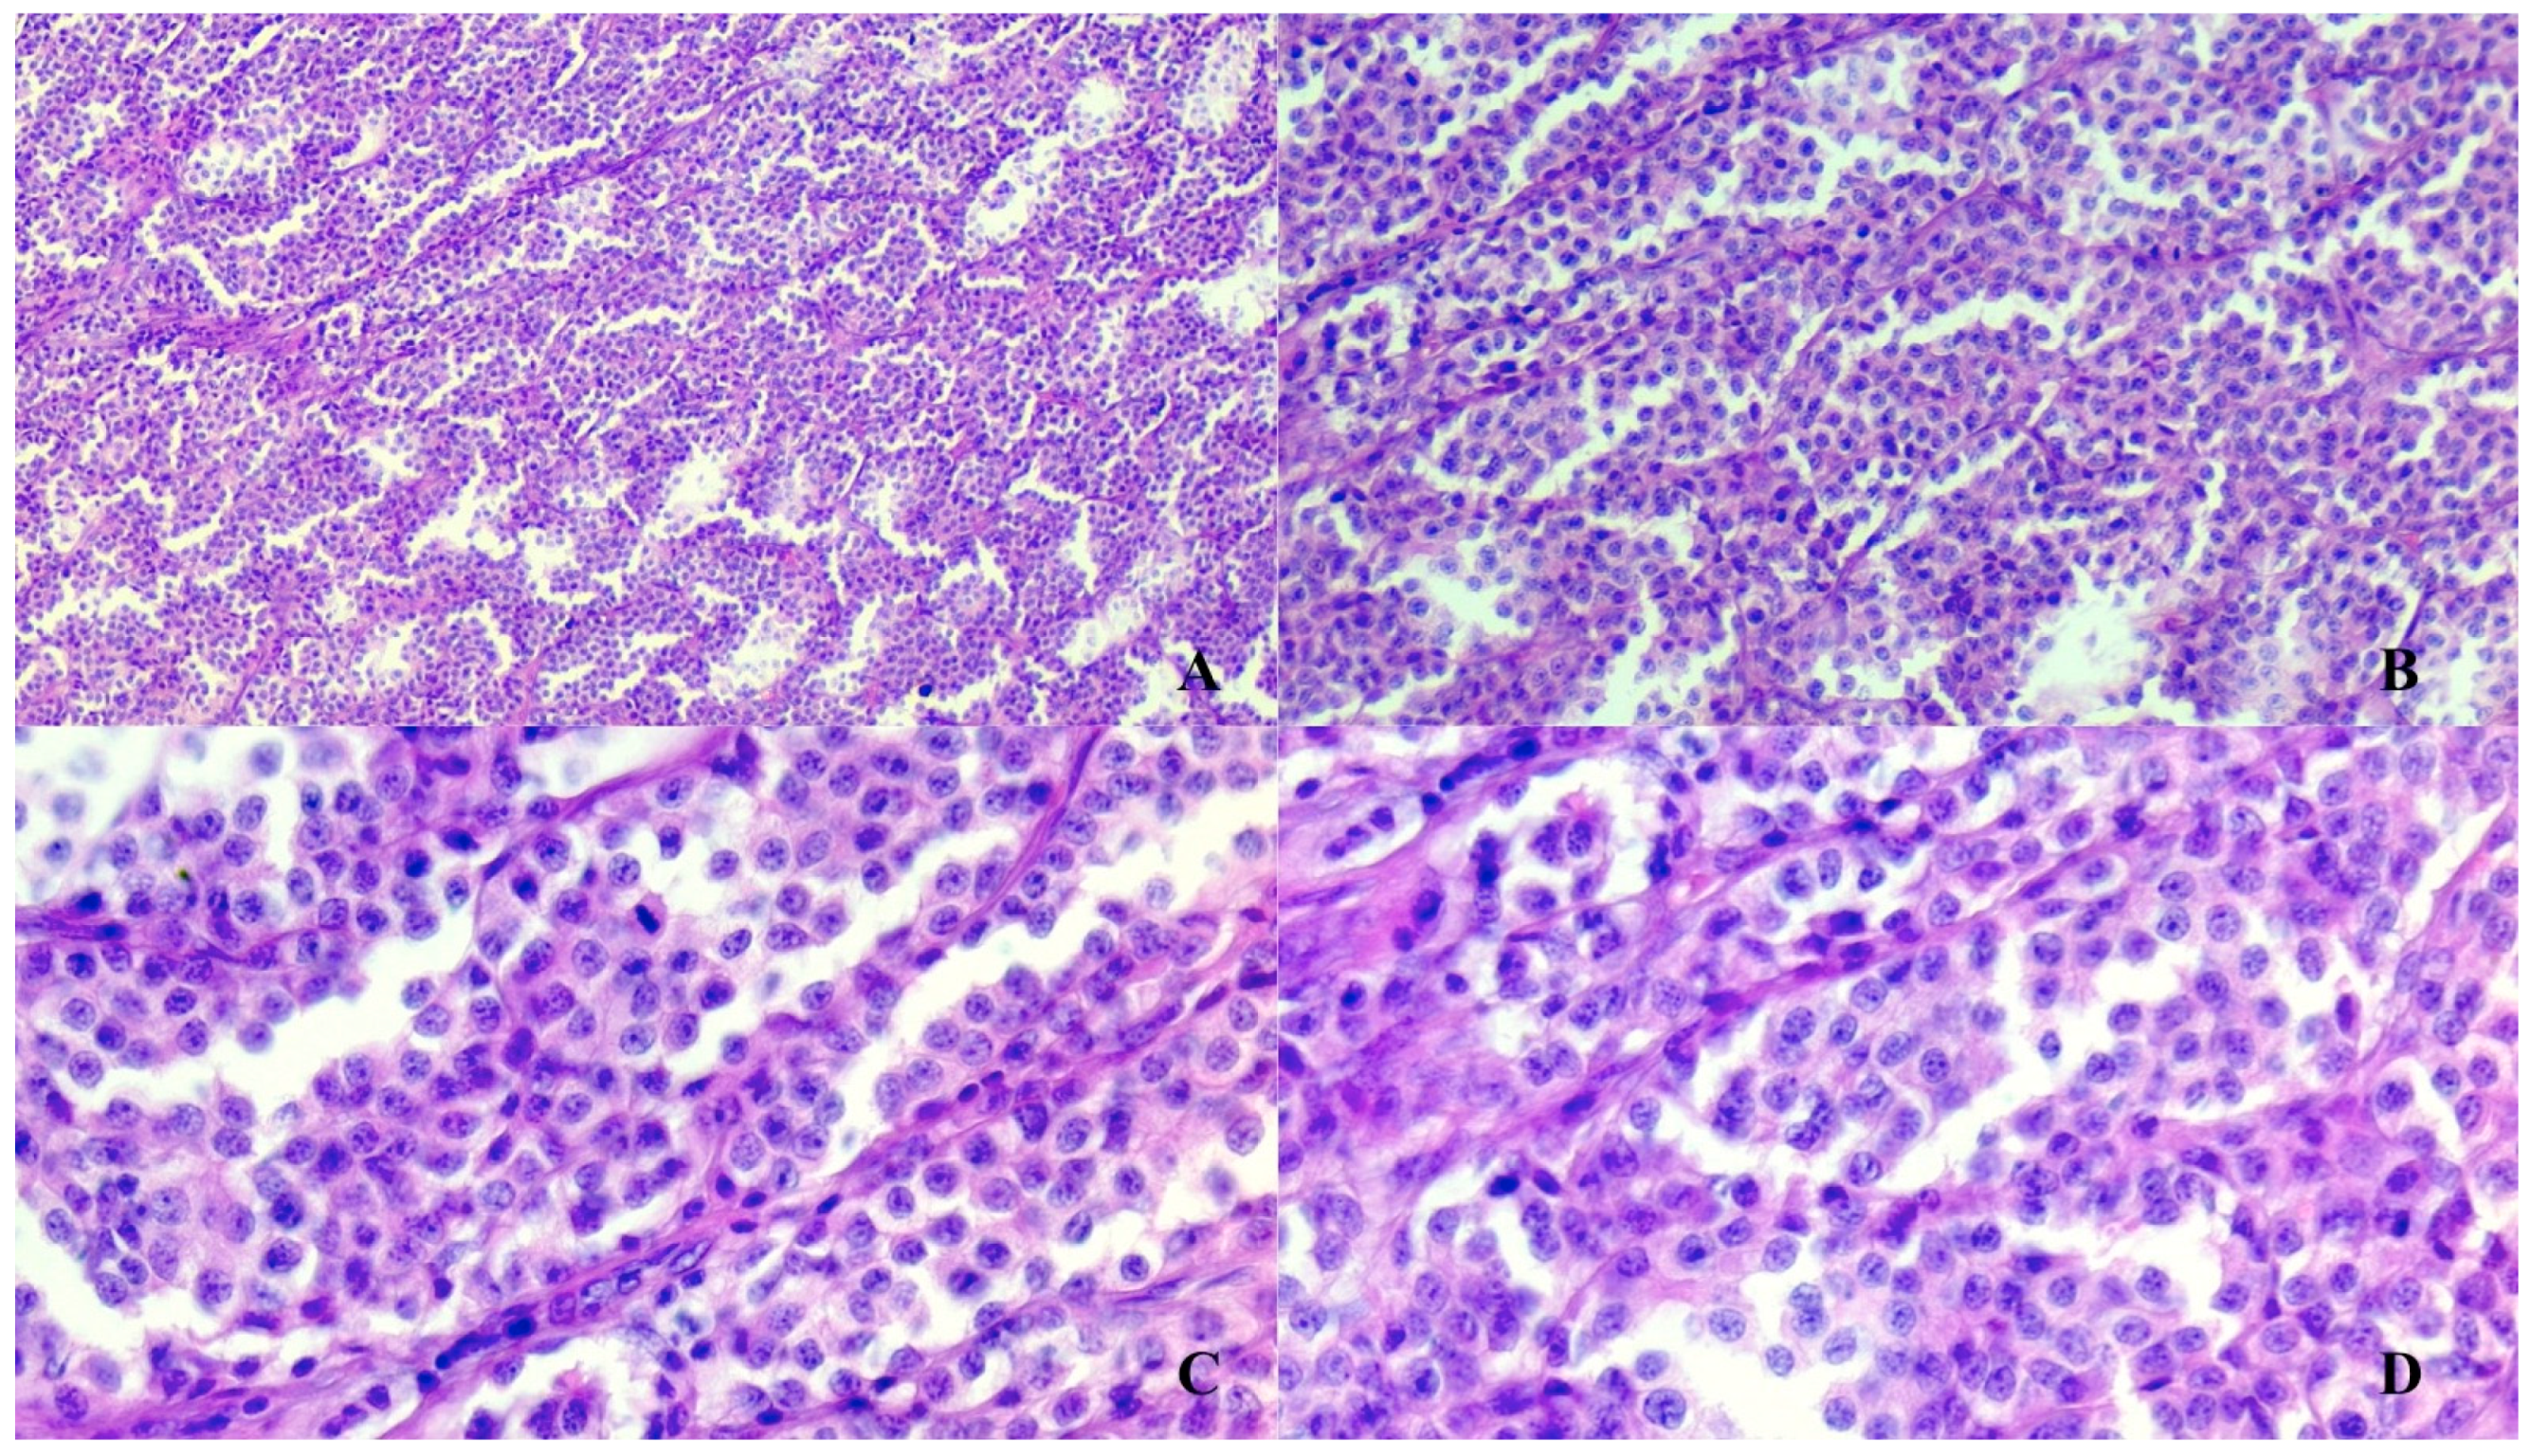

The tumor had diffuse strong cytoplasmic immunostaining to anti-chromogranin, anti-synaptophysin, anti-vimentin and anti-NSE, while anti-GFAP showed only multifocal small linear streaks among neoplastic cells, interpreted as cytoplasmic processes of sustentacular cells. The tumor was negative to anti-cytokeratin (Figure 3).

Figure 3.

Paraganglioma features for immunohistochemical markers. (A) Anti-synaptophysin. (B) Anti-Chromogranin. Anti-NSE. (C) Anti-NSE (D) Anti-Cytocheratins. (A) (magnification 10×), (B,C) (magnification 20×) figures show a diffuse cytoplasmic immunostaining marking of neoplastic cells of paraganglioma. (D) (40× magnification) anti-cytokeratin stain shows a very mild and focal positivity (negative) stain. Immunoperoxidase.

Histopathology revealed neuroendocrine cells with a nest organization as well as the presence of a fibrovascular stroma []. In addition, to make a correct and definitive diagnosis of this tumor, neoplastic cells must be positive for some immunohistochemical markers such as chromogranin A, NSE and Synaptophysin []. In fact, using immunohistochemical investigations, neoplastic cells are positive in different ways for the following biomarkers: Chromogranin A, NSE, SYN and GFAP. Chromogranin A, NSE and Synaptophysin are strongly expressed in neoplastic cells, while GFAP is poorly expressed. Nevertheless, it is useful for the final diagnosis since its expression decreases with tumor progression.

The immunohistochemical investigations performed were of fundamental importance, which detected a constant positivity to the markers against Synaptophysin, chromogranin, NSE and vimentin, while cytokeratin always gave a mild, sporadic marking. The diagnosis of certainty against a neuroendocrine tumor was reached thanks to the detection of the constant positivity of the neoplastic cells towards the three main markers used for neuroendocrine cells: Synaptofysin, Chromogranin and NSE, of which chromogranin is the endowed marker of higher specificity towards these cells, with the main expression at cytoplasmic granules level. This positivity may be milder in poorly differentiated tumors and with a higher degree of malignancy, but the positivity towards synaptophysin constant in all forms of neuroendocrine tumors with various degrees of malignancy, did not leave interpretative and diagnostic doubts in this case.

The neuroendocrine sustentacular cells also gave a multifocal positivity towards GFAP, testifying to the good differentiation of the paraganglioma in question, while the presence of the connective septa supporting the tumor allowed to detect a relative positivity also towards vimentin. Finally, the mild, focal, sporadic positivity for cytokeratin allowed us to exclude the presence of a form of neuroendocrine carcinoma.